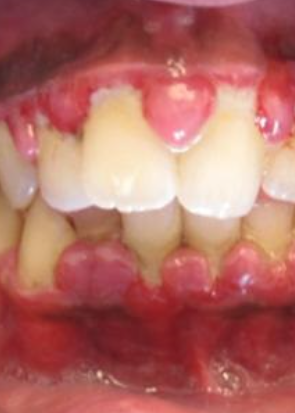

치은염

잇몸병의 초기 상태로, 잇몸의 염증이 연조직에만 국한되어 있어 간단한 치료로도 회복이 가능합니다.

치태 내의 세균들이 만들어낸 독소가 잇몸에 염증을 일으켜 잇몸이 뻘겋게 붓고, 치아를 닦을 때 잇몸에서 피가 나고, 입 냄새가 납니다.

2. 치태에 의하지 않은 잇몸 염증

사춘기, 생리, 임신, 당뇨 같은 호르몬 변화나 백혈병 같은 혈액질환, 고혈압약, 항경련제, 면역억제제, 경구피임약 등 약물 복용의 영향으로 생길 수 있습니다.